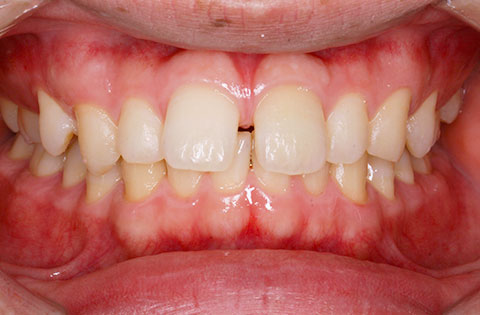

矯正後

矯正後 正面

矯正後 右側

矯正後 左側

主訴 正中が開いている。咬み合わせが深く歯肉を咬んでしまう。

年齢 20代

治療法 上下顎マルチブラケット装置

抜歯の有無 なし

治療期間 1年6ヶ月